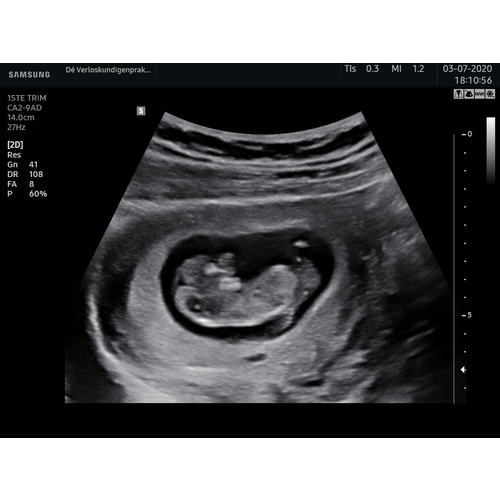

Voor 3D is het vruchtje dan ook nog te klein... Het is amper een paar centimeter groot én in volle ontwikkeling. Helemaal niks raar aan de hoofdvorm, en allesbehalve een reden om je zorgen over te maken.

3d? Met zo'n vroege zwangerschap?

Meeste mensen doen dit pas tussen 24-30 weken want dan is de beste tijd om een 3d echo te doen. Ik ken persoonlijk niemand die dit zo vroeg heeft gedaan